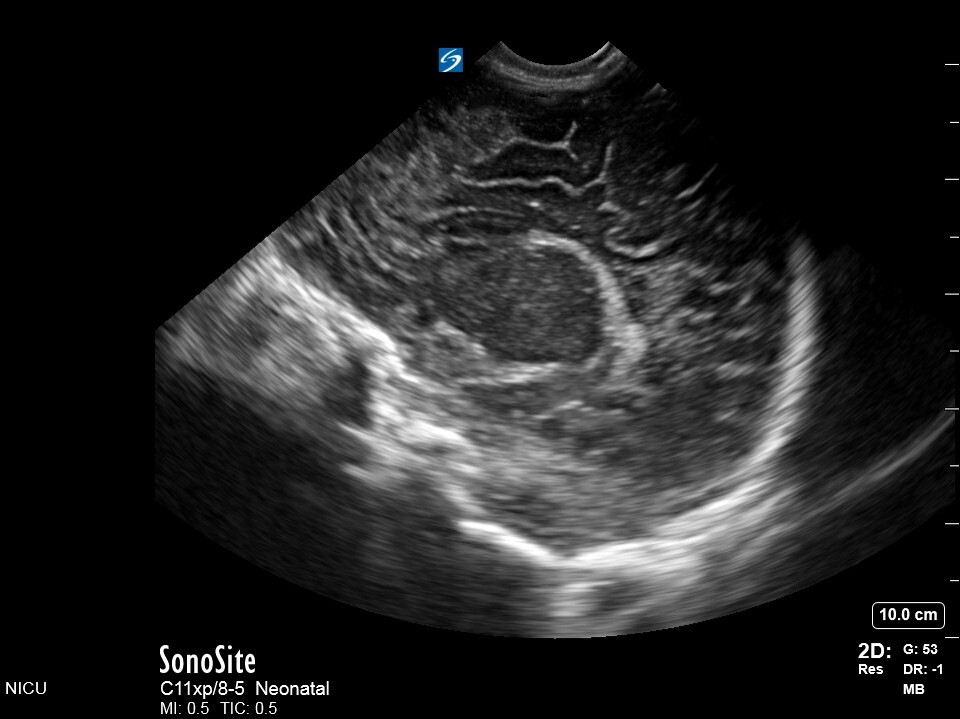

Neonatology S2 1 Image